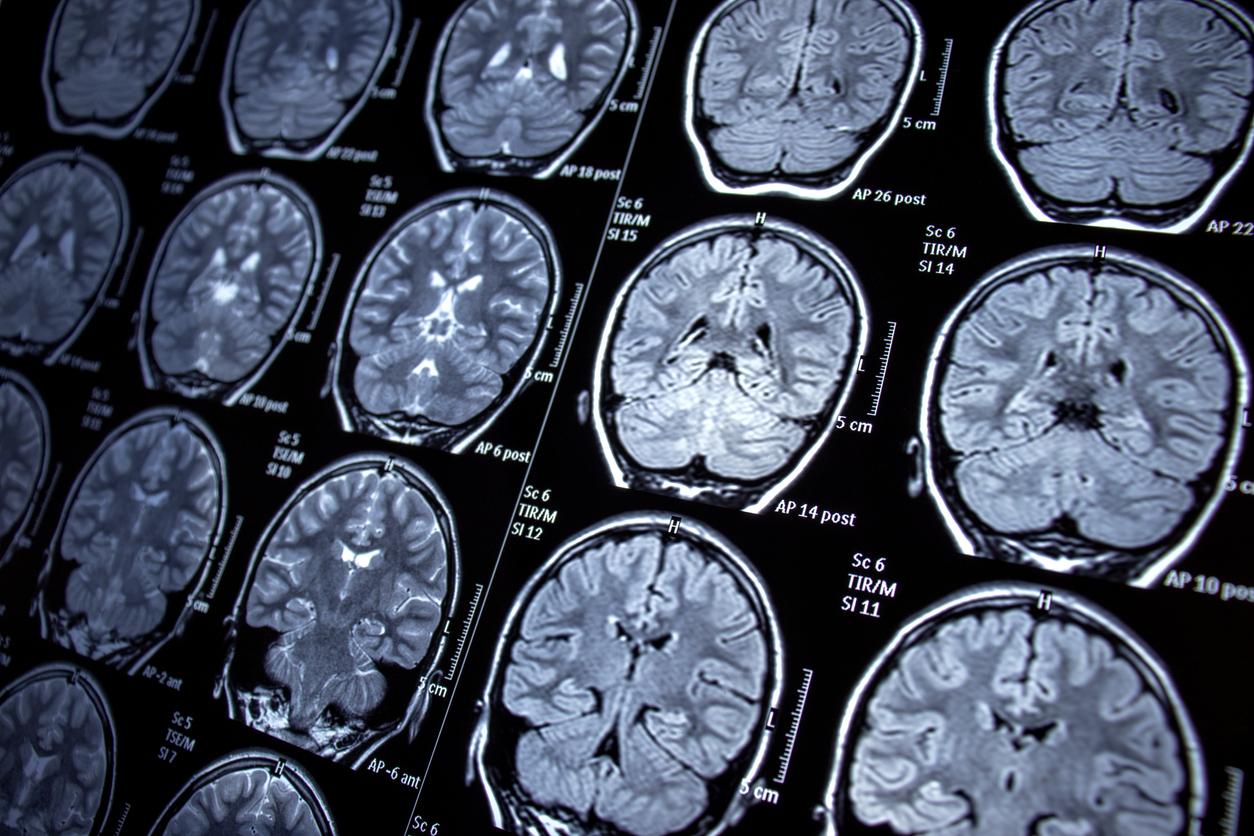

La maladie d’Alzheimer est une pathologie neurodégénérative. Ses symptômes sont parfois difficiles à analyser, même pour un médecin, car le diagnostic est complexe. Il faut tout d’abord identifier les trouves cognitifs du patient, en s’appuyant sur le ressenti et les difficultés de la personne - ceux de son entourage également - ainsi que sur des tests de mémoires, d’état mental et d’autres fonctions cérébrales. En croisant toutes ces données avec d’autres facteurs tels que l’âge, le praticien pourra poser un diagnostic.

Il y a deux types de lésions qui détruisent les neurones des patients atteints de la maladie d’Alzheimer : celle des plaques amyloïdes autour des neurones et la dégénérescence neurofibrillaire. Mais c’est le second type de lésion qui permet de mieux comprendre le cas de Chris Hemsworth.

La dégénérescence neurofibrillaire est due à la protéine Tau. Celle-ci est naturellement présente dans l’organisme mais, chez les patients atteints de la maladie d’Alzheimer, cette protéine est modifiée. Ainsi, elle désorganise la structure des neurones et produit une dégénérescence neurofibrillaire qui aboutit à leur mort.